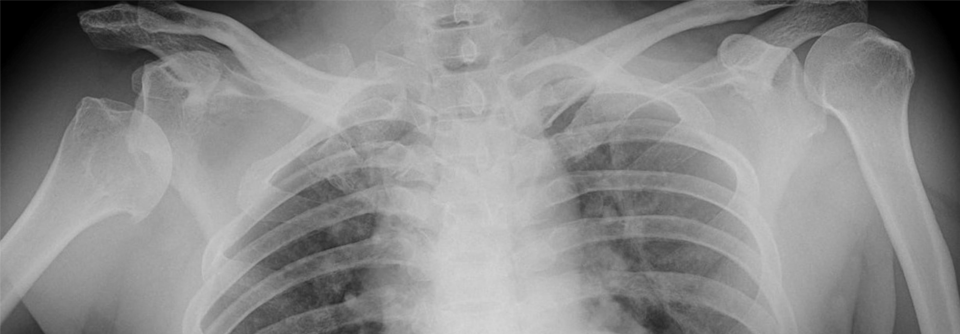

Ausgekugelte Schulter

Keine langwierige Physiotherapie erforderlich

Eine ausgekugelte Schulter wird zunächst meist konservativ behandelt – sofern es sich um die erste Verletzung dieser Art handelt. Ob dabei eine…